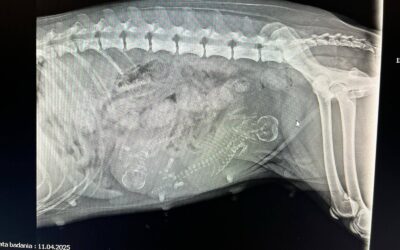

11.04.2025

Dzisiaj odwiedziliśmy klinikę weterynaryjną SkaVet na zrobienie zdjęcia i sprawdzenie stanu ciąży. Ku wszystkich zaskoczeniu i wielkości Sigi okazuje się, że będą dwa bąbelki.